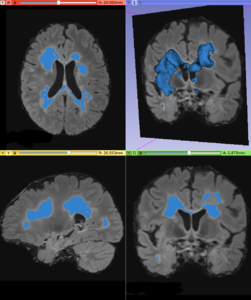

This module offers an implementation of a recent Multiple Sclerosis lesion segmentation approach based on a unsupervised method described by Cabezas et al. [1]. This module is intended to be used with FLAIR and T1 MRI volumes, which the MS lesions can be detected.

• Using T1 and FLAIR MRI volumes, it can be possible to detect abnormal voxel signal using a parametric strategy, which delineates white matter signals that does not belongs to the majority neighborhood pattern. More details can be found in the original paper [2]

• Output a global lesion mask